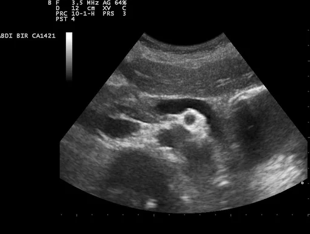

Ultrasound, Diagnostic